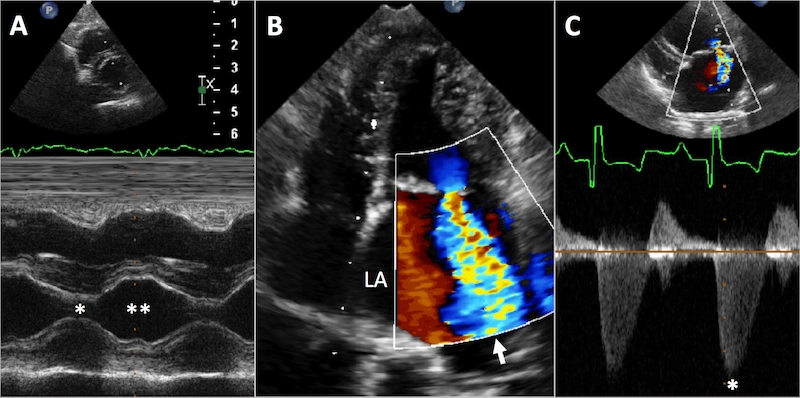

Kliniğimizde, kardiyolojik rahatsızlık şüphesi ile gelen sevimli dostunuzun öncelikle hekimlerimiz tarafından genel muayeneleri yapılır, muayene esnasında strese girmemelerine özen gösterilir. Muayene sonucunda hekimimizin yönlendirmesi üzerine Ekokardiyografi, Renkli Doppler Ultrasonografi, EKG, Dijital Röntgen ile Detaylı Kalp Muayenesi, Kardiyak Panel Testleri, Tansiyon Ölçümü yapılarak sevimli dostunuzda meydana gelmiş olabilecek kalp ve damar hastalıklarının teşhis ve tedavileri gerçekleştirilir.